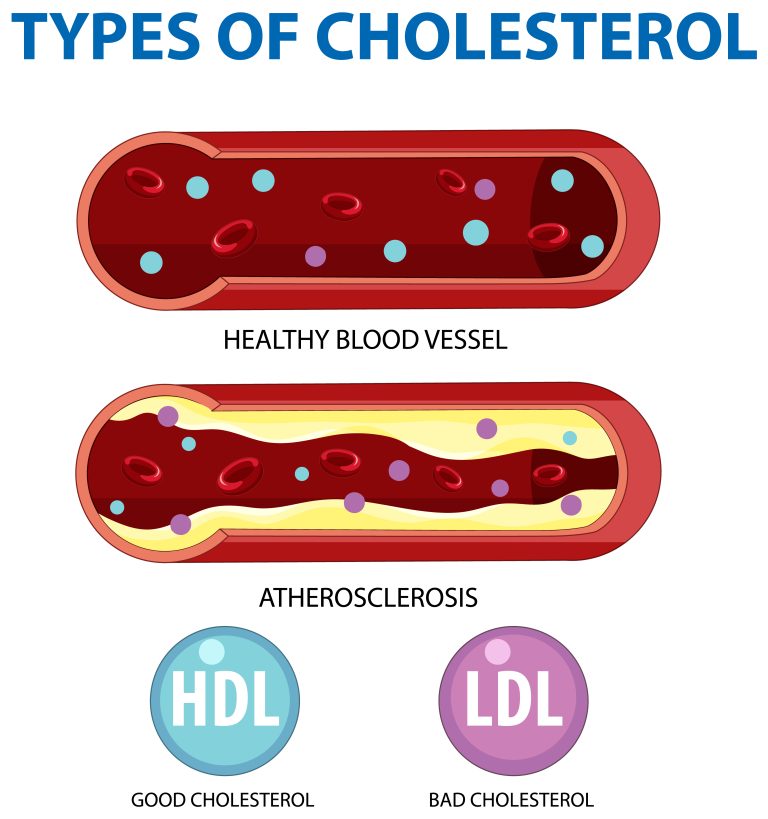

Desvendando Mitos e Verdades sobre o Colesterol

O colesterol é um componente essencial do nosso corpo, dessa forma desempenhando papéis vitais na formação de membranas celulares e na produção de hormônios. No

Como age a sinvastatina?

A sinvastatina pertence a uma classe de medicamentos chamados estatinas, que são amplamente utilizadas para reduzir os níveis de colesterol no sangue. Portanto, o mecanismo

Efeitos Colaterais da Sinvastatina

A sinvastatina é um medicamento amplamente prescrito para reduzir os níveis de colesterol e prevenir doenças cardíacas. Embora seja eficaz em muitos casos, é importante